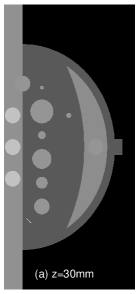

II Breast Phantom

A breast phantom was designed to provide a basis for algorithm comparison. It consists of objects with different geometric shapes to allow for analytic computation of the projection data. The overall shape of the compressed breast of 50 mm thickness is modeled by a truncated ellipsoid. Attenuation coefficients at a photon energy of 30 keV [10] were used for phantom materials simulating the fibroglandular, tumour and muscle tissues, as well as microcalcifications in the breast. In Fig. 1, we display the phantom images within 2D planes specified by (a) mm, by (b) mm, (c) mm, and (d) mm, respectively. As shown in Fig. 1a, the crescent-shaped region, representing the fibroglandular tissue region of the breast, is attached to a rectangular slab of higher attenuation, simulating the pectoralis muscle. It can be observed in Fig. 1 that numerous test objects of different sizes and contrast levels are embedded in the phantom for simulating mass lesions and microcalcifications. In particular, a row of three ellipsoids is embedded in the pectoralis muscle (see Fig. 1(b)), with equal in-plane diameters but varying flatness, thus allowing one to evaluate whether shapes of equal in-plane profile, but different in-depth profiles, can be resolved. Furthermore, six spheres of different diameters, ranging from 5 mm to 15 mm, are equally distributed in the fatty area of the breast (see Fig. 1(c)). It can also be observed in Fig. 1(d) that three pairs of stacked spheres of identical diameter mm are embedded in the breast region with different spacings of , , and , respectively, for these pairs. Finally, two clusters of small spheres of diameters 0.3 mm and 0.15 mm are included to model microcalcifications.